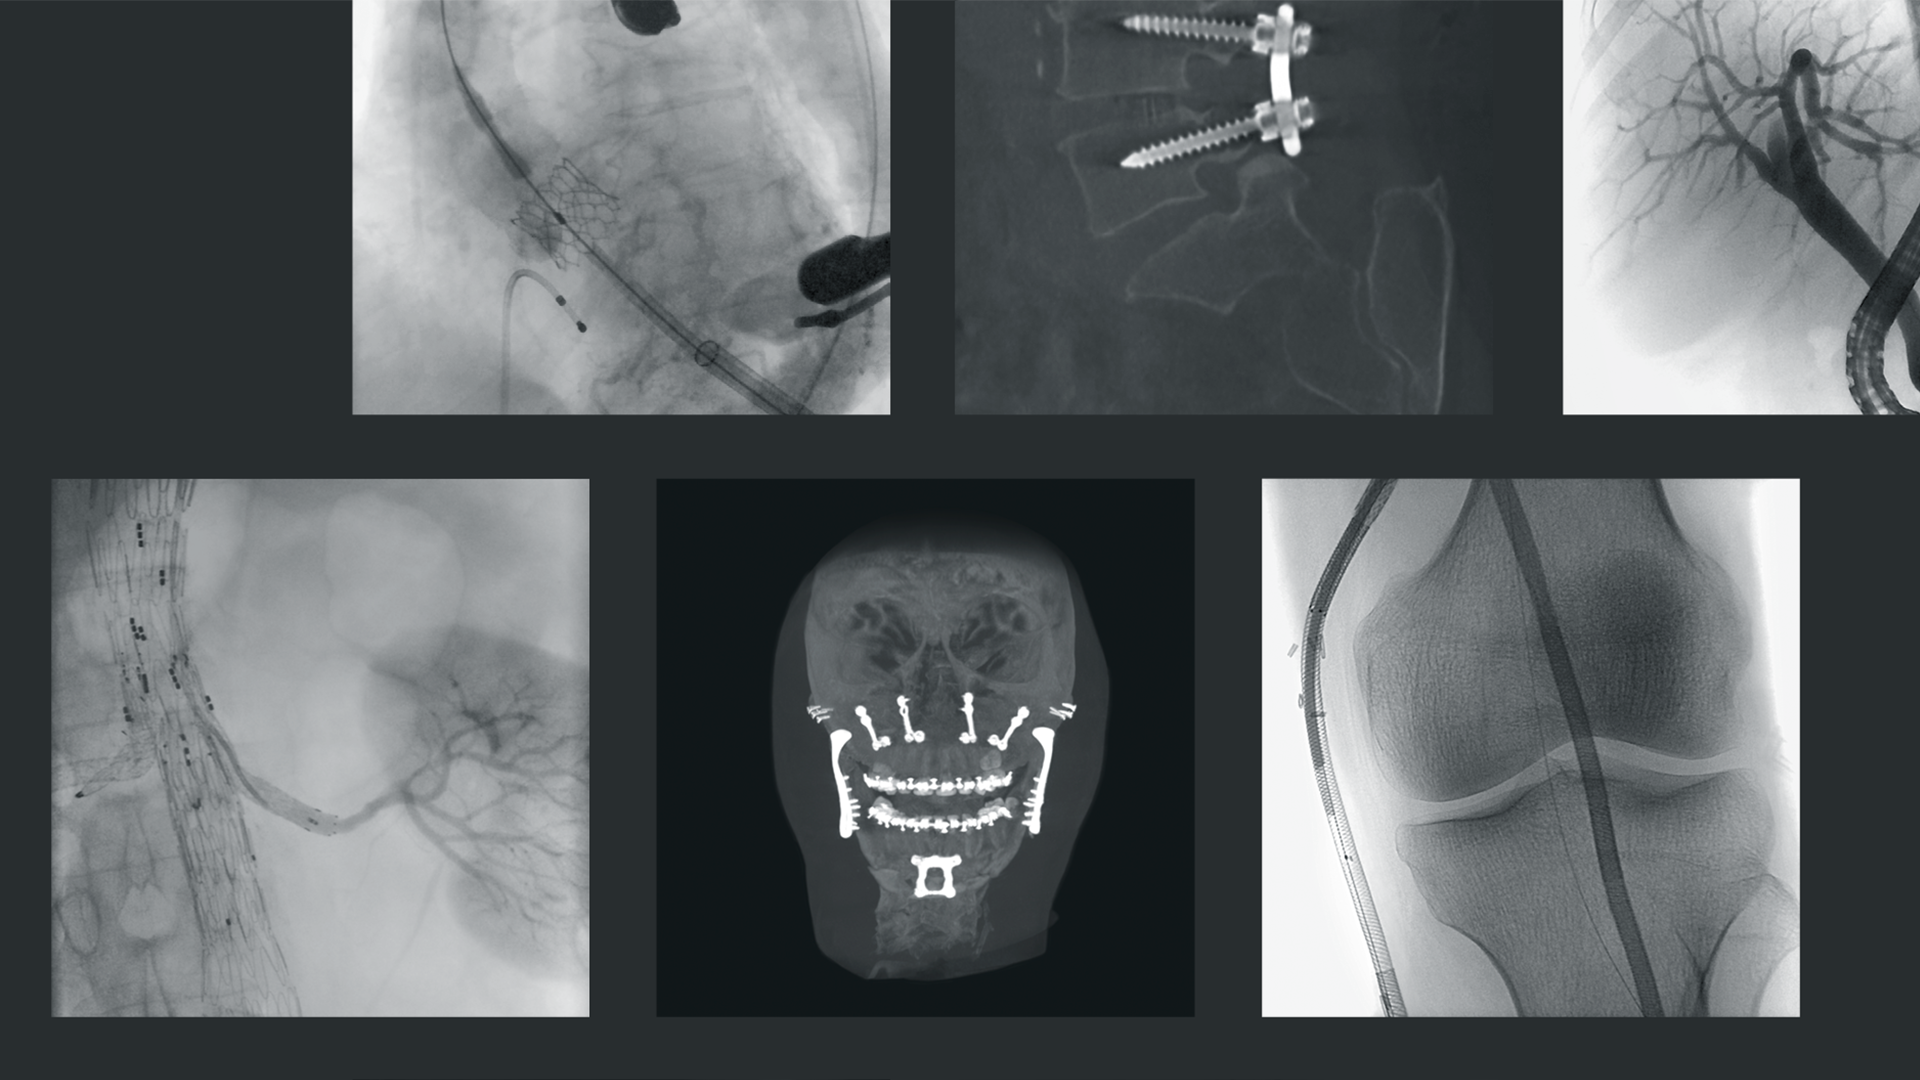

Desde 1972, a Ziehm Imaging desenvolve e produz soluções de imagem móveis baseadas em raios X, sempre com o objetivo de definir novos padrões tecnológicos. Nosso amplo portfólio inclui sistemas compactos, dispositivos para imagem 3D e laboratórios móveis de cateterismo.

Com qualidade de imagem excepcional e grande flexibilidade, tornamos o trabalho clínico diário mais seguro e eficaz em todo o mundo. Como resultado, os desfechos dos tratamentos para os pacientes podem ser continuamente otimizados.

A Ziehm Imaging apoia profissionais médicos com sistemas de imagem inovadores que possibilitam um fluxo de trabalho suave, rápido e confiável. Nossos arcos em C móveis são usados não apenas em cirurgia espinhal, ortopedia e traumatologia, mas também em cirurgia vascular e cada vez mais em broncoscopia, bem como no apoio às terapias oncológicas.

As soluções podem ser adaptadas individualmente aos diversos requisitos clínicos e oferecem a mais alta qualidade de imagem. Desta forma, ajudamos usuários de várias especialidades a otimizar fluxos de trabalho e a oferecer o melhor cuidado possível. Contribuímos para o sucesso do tratamento mesmo nas condições mais exigentes. Trabalhamos continuamente no desenvolvimento de soluções inovadoras e aspiramos explorar novas aplicações clínicas no futuro.

Graças à colaboração estreita com nossas empresas subsidiárias, nosso portfólio de produtos fica idealmente complementado. Orthoscan expande nossa gama de produtos com mini arcos em C inovadores, projetados especialmente para extremidades, ortopedia e cirurgia de trauma. Therenva fornece soluções inovadoras para planejamento eficiente e navegação segura em procedimentos minimamente invasivos nos campos cardiovascular e endovascular.

Um marco de nossa colaboração é a primeira navegação endovascular com fusão de imagem integrada em um arco em C móvel. Isso combina o hardware de última geração da Ziehm Imaging com o software inteligente da Therenva em uma solução que simplifica o trabalho diário na sala de operação, permitindo navegação precisa dentro do campo estéril, e economiza espaço no centro cirúrgico.